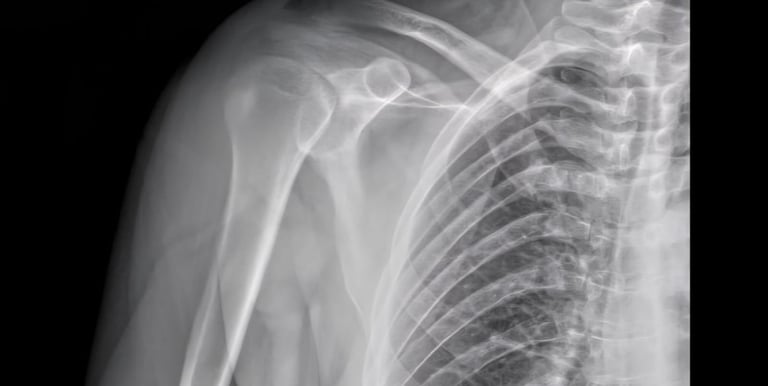

Shoulder X-rays

Advanced digital imaging for shoulder dislocations, rotator cuff concerns, and joint injuries. We deliver clear, detailed views for orthopedic evaluations and reporting.